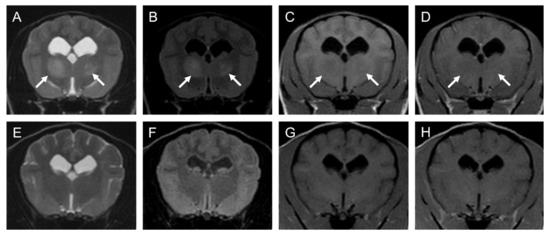

2.1. Case 1

2.2. Case 2